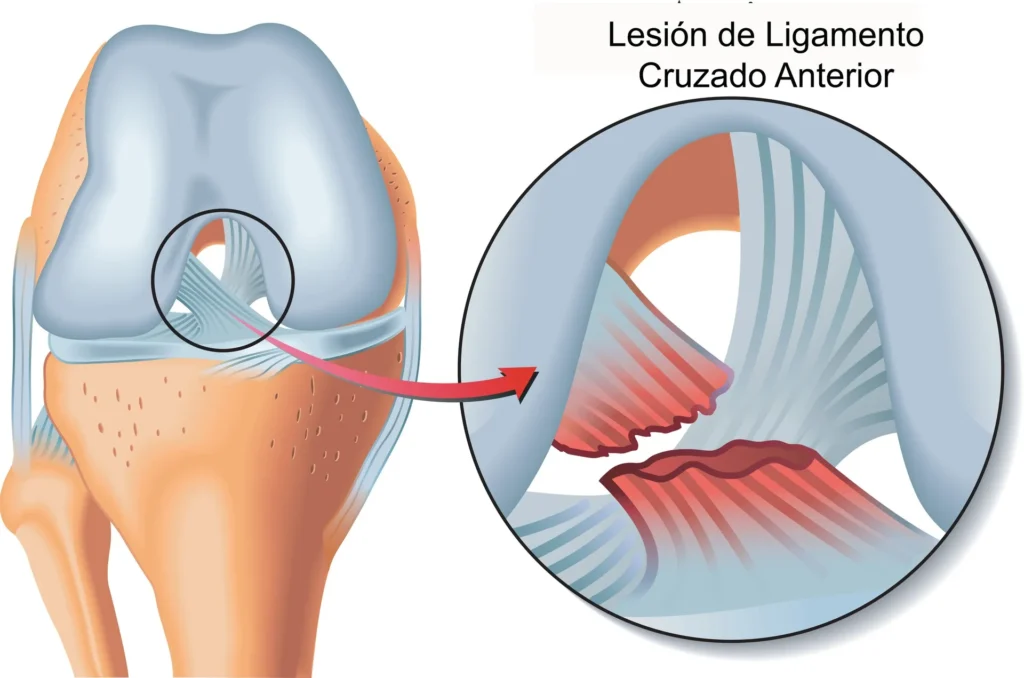

A lesão do Ligamento Cruzado Anterior (LCA) ocorre quando as fibras que compõem essa estrutura se rompem parcial ou totalmente.

Esse rompimento compromete a estabilidade do joelho e interfere diretamente na sua função.

O LCA pode se lesionar tanto por traumas diretos quanto por movimentos bruscos e inadequados, mesmo sem contato físico.

A lesão do LCA ocorre quando o ligamento é esticado além do limite e se rompe parcial ou totalmente.

Existe diferença entre ruptura parcial e total do LCA?

Sim.

Na ruptura parcial, apenas uma parte do ligamento é lesionada, e o joelho pode manter certa estabilidade.

Já na ruptura total, o ligamento perde completamente sua função, causando instabilidade, dor e dificuldade para sustentar o peso corporal.

O tratamento varia conforme o tipo e a extensão da lesão.